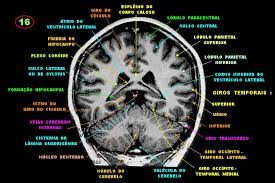

Imagem e estruturas Corte Coronal RM.

Imagem e estruturas Corte Coronal RM - Posterior.